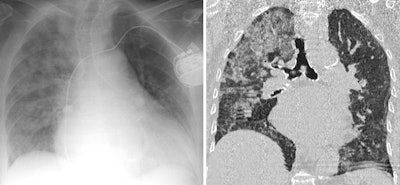

Be sure to check for previous examinations, they recommended. Chest x-ray abnormalities showing a few hours of onset are typical in pulmonary hemorrhage, cardiogenic edema, transfusion-related acute lung injury, and aspiration. Also, check for previous cardiac size, and look for signs of fibrosis in previous examinations as a clue to acute exacerbation of fibrosis.

"Check for a typical pattern," the authors advised. "The presence of typical chest CT patterns can make the diagnosis straightforward, however they gain specificity when presenting in a characteristic clinical background. The main abnormalities, their distribution, and ancillary findings confirm the specific patterns."